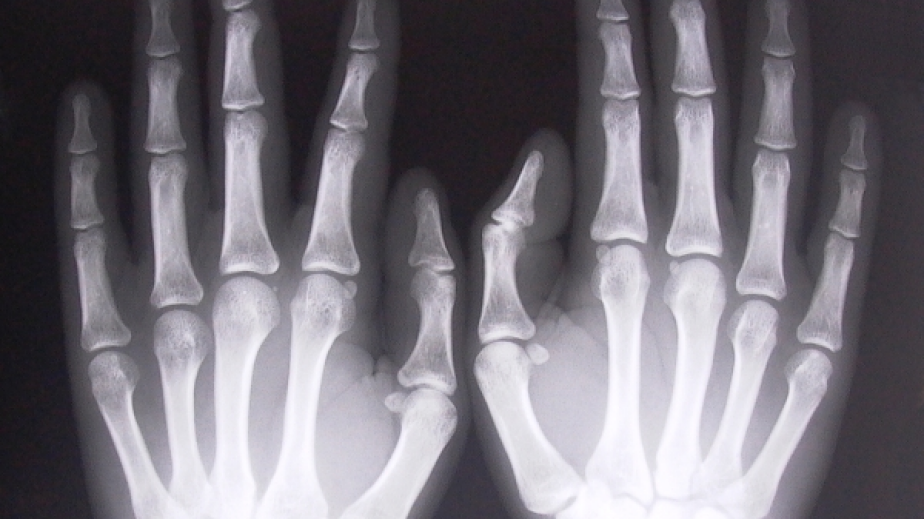

При 21% от общо изследваните 152-ма души в Пернишко е открито заболяването остеопороза, съобщиха от Регионалната здравна инспекция.Прегледани са били хора от 6-те общини на областта. 30% пък са пациентите с остеопения.Резултатите са от проведените информационни скринингови кампании за определяне на личния риск от остеопороза и измерване на костна плътност. Средната възраст на изследваните е 63 г.На всички участници от  РЗИ – Перник са осигурили информационни материали, чрез които да научат повече за остеопорозата и за профилактиката на заболяването. Изследваните лица, при които се установи отклонение от нормата са консултирани от лекари.За периода от месец април до месец септември в цялата страна се провeждаха кампании за определяне на личния риск от остеопороза и измерване на костна плътност. Кампаниите се организираха в сътрудничество между Министерство на здравеопазването, Асоциацията на пациентите с остеоартроза и Националното сдружение на общопрактикуващите лекари в България /НСОПЛБ/ и се подпомагат от Българския фонд за жените. Изследванията се осъществяват с апаратура, закупена за целите на провеждането на скрининг за ранно установяване на риска от остеопороза.